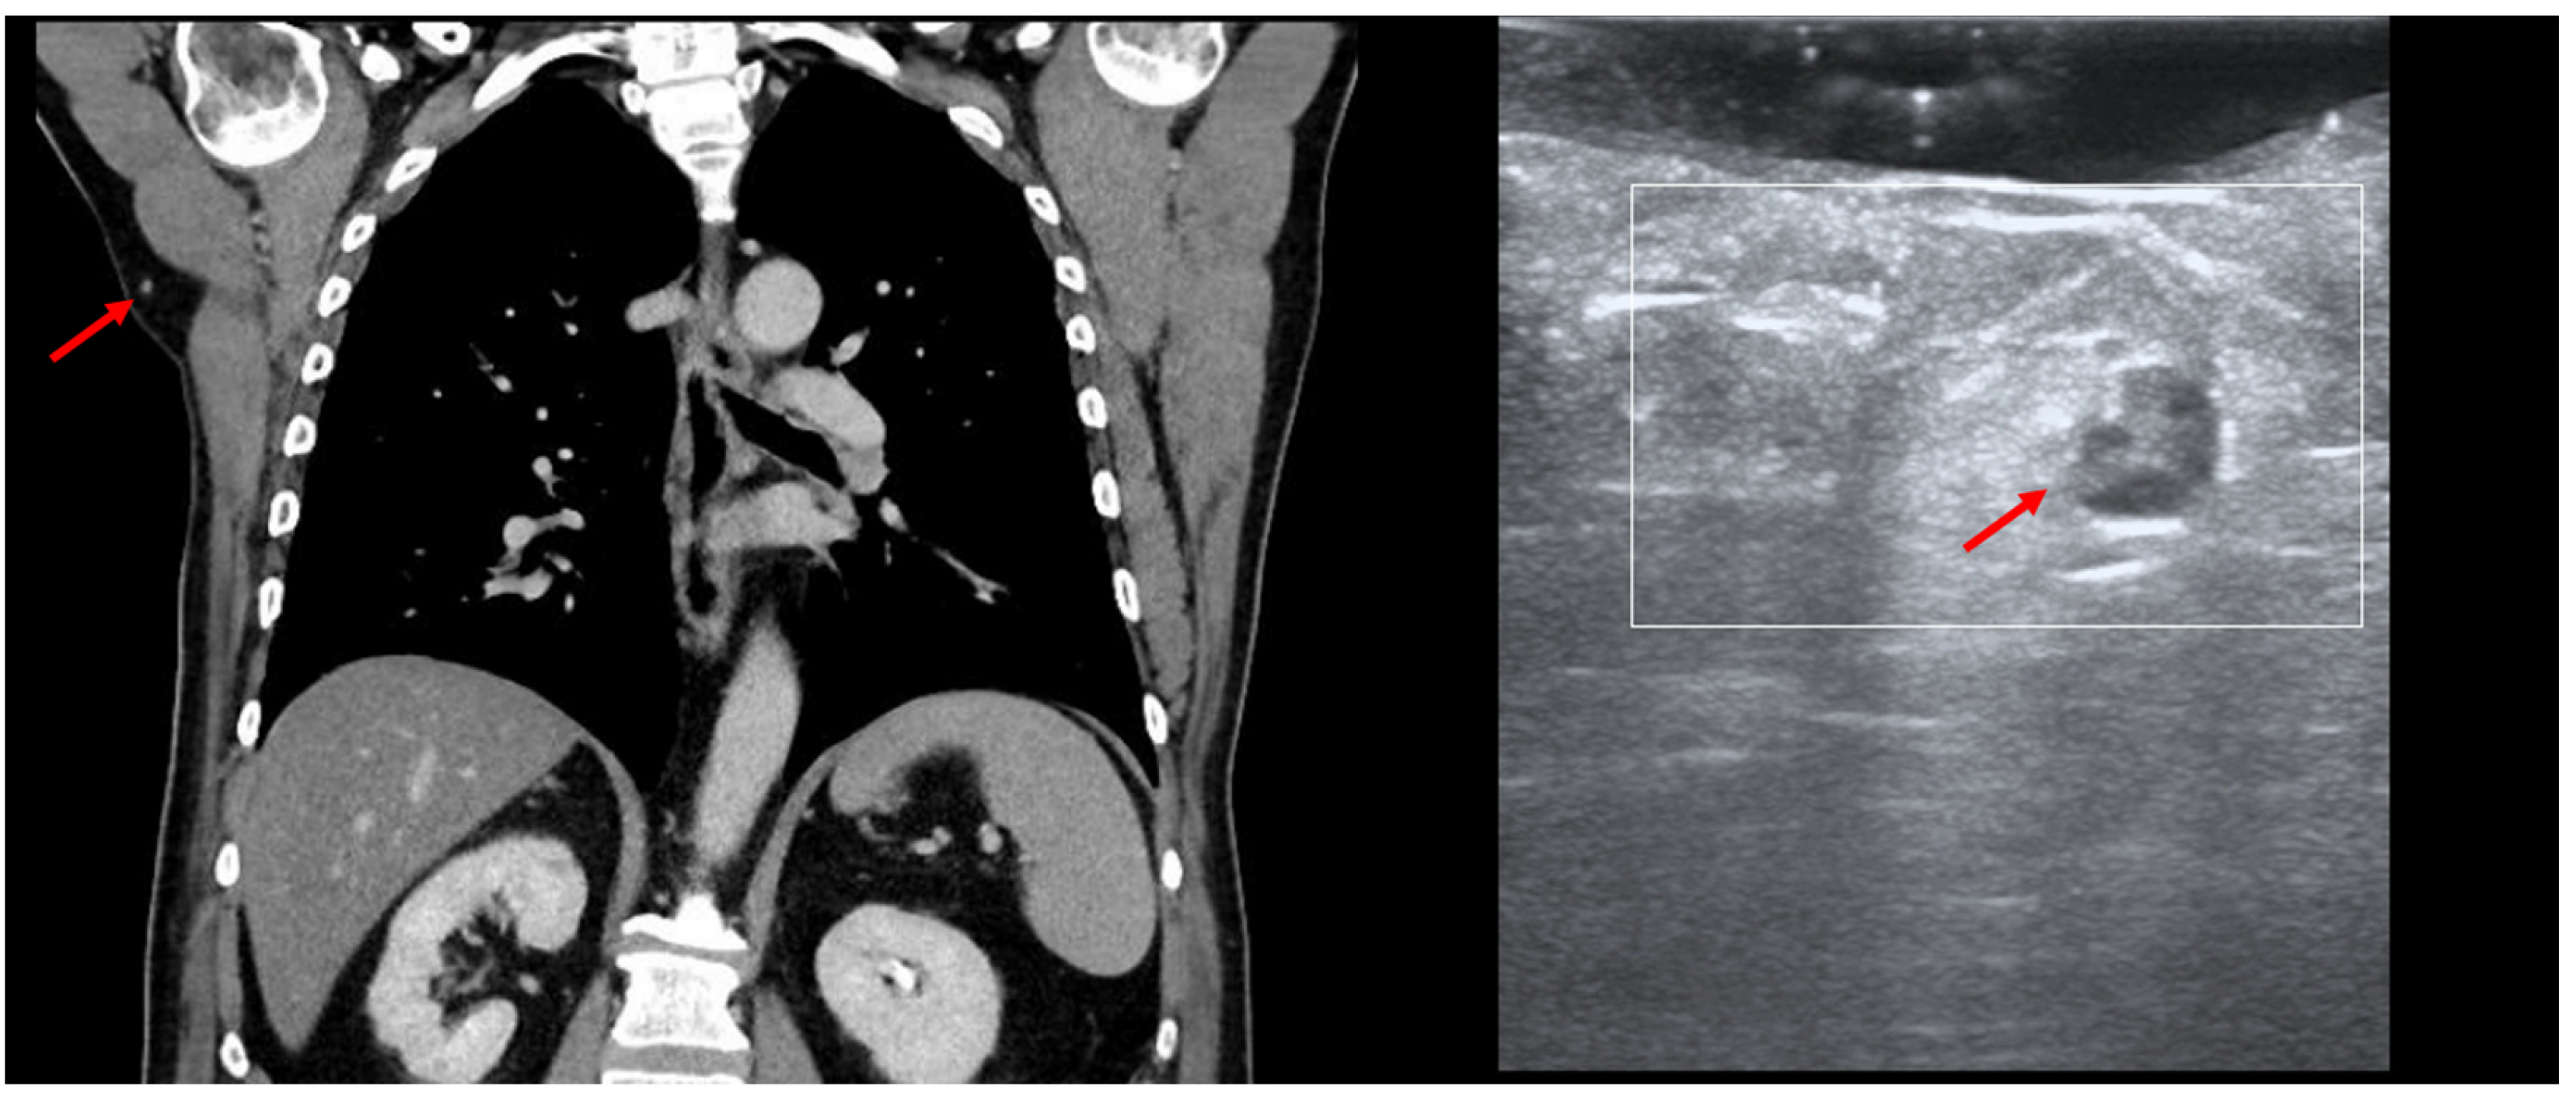

10. Avoidance of Unnecessary Surgeries due to Patient Up-Staging